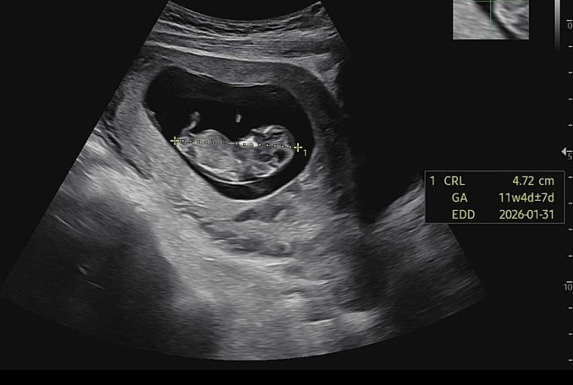

11주4일인데 딸일까요 아들 일까요??